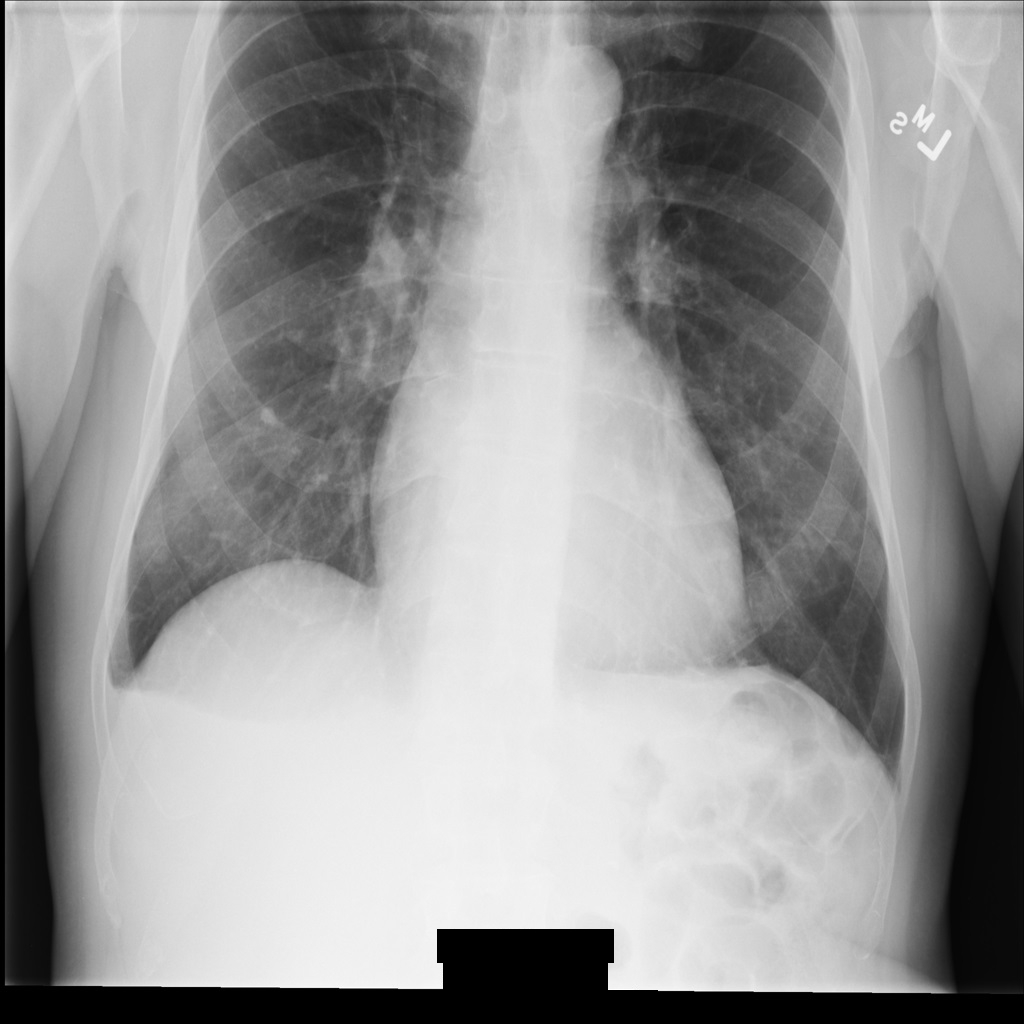

示例图片

本页面中的某些示例包含去标识化后的图片输出。每个示例都使用以下原始图片作为其输入。您可以将每个去标识化操作的输出图片与该原始图片进行比较,以查看该操作的效果: